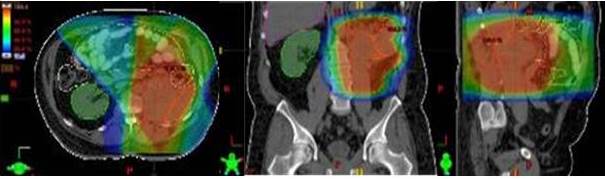

El grupo de sarcomas en retroperitoneo estuvo conformado por 26 pacientes, en promedio se encontraban finalizando la quinta década de la vida, no hubo diferencia significativa en cuanto al sexo, fueron más frecuentes los liposarcomas (53,8 %) seguidos de los leiomiosarcomas (19,5 %) y sarcomas inespecíficos (11,5 %). Según el estadio de la enfermedad, predominaron los IIIB (34,6 %) seguidos de los IB (30,7 %). Todos los pacientes fueron llevados a mesa operatoria, en la mayoría de los casos se realizó cirugía en una sola oportunidad (88,4 %) y sólo 3 pacientes ameritaron más de 2 cirugías. En el 53,8 % los márgenes quirúrgicos fueron reportados positivos, en el 38,4 % se obtuvieron márgenes negativos y en 2 casos no se especificaron. Sólo 3 pacientes recibieron tratamiento sistémico en sus distintas modalidades. En todos los pacientes la radioterapia se realizó como modalidad posoperatoria, en la mitad de los casos se utilizó la técnica de planificación conformada tridimensional (66,7 %) seguido de la convencional (19,2 %), la dosis total promedio fue de 4 750 cGy (Cuadro 2 y Figura 5).

Las complicaciones agudas más frecuentes fueron la dermatitis grado I y síntomas gastrointestinales inferiores grado I en un 26,9 % de los casos (Cuadro 3). En cuanto a las crónicas un paciente presentó toxicidad gastrointestinal inferior grado II y otro desarrolló toxicidad gastrointestinal superior grado II.

El 57,6 % de los pacientes se encuentran vivos sin enfermedad, 4 se mantienen vivos con enfermedad, mientras que sólo 7 fallecieron a causa de su patología (Cuadro 6). Cabe acotar que el promedio de dosis de los pacientes sin enfermedad fue 5 400 cGy mientras que el promedio de los vivos y fallecidos con enfermedad fue de 5 000 cGy independientemente de los márgenes quirúrgicos. El tiempo promedio de seguimiento fue de 44,4 meses y la mediana 32,2 meses.

La sobrevida libre de enfermedad fue de 51 % y la sobrevida global se reportó en 75,5 % (3).